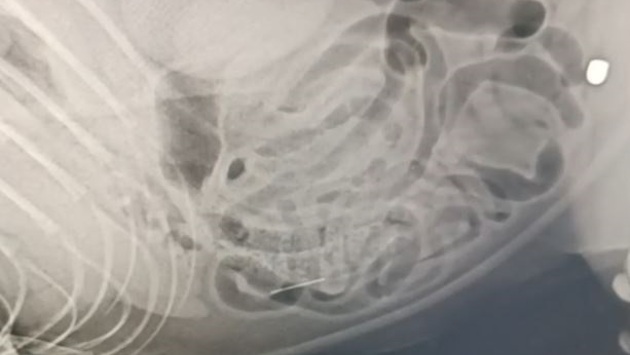

Ростовская область, 26 февраля 2025. DON24.RU. В Шахтах волонтеры борются за жизнь кота, сбитого автомобилем. У животного диагностированы черепно-мозговая травма, перелом челюсти, вывих бедра, а также практически выбитый глаз. Кроме того, при обследовании в теле четвероногого обнаружили пулю, застрявшую в бедре, и иглу в брюшной полости. «Свои три из девяти жизней этот кот потерял точно. Как он выжил, одному Богу известно, иголка в любой момент могла порвать ему кишечник, и кот умер бы от перитонита. Плюс удар машиной. Мы все прекрасно знаем, что сбитые котики встречаются крайне редко, не выживают они после встречи с авто... А тут чудо на чуде!» – рассказали в реабилитационном центре бездомных животных «Святобор». Ранее в Неклиновском районе спасатели вытащили пса, провалившегося в пятиметровую расщелину.